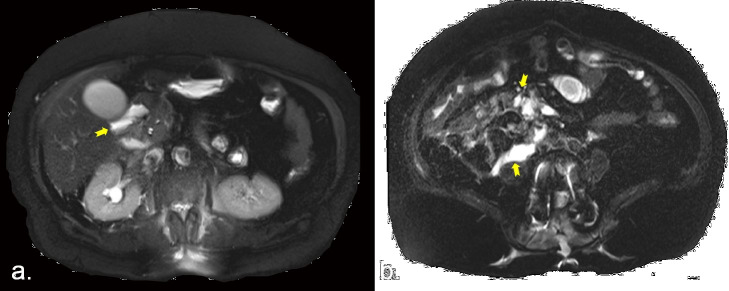

Abstract Image